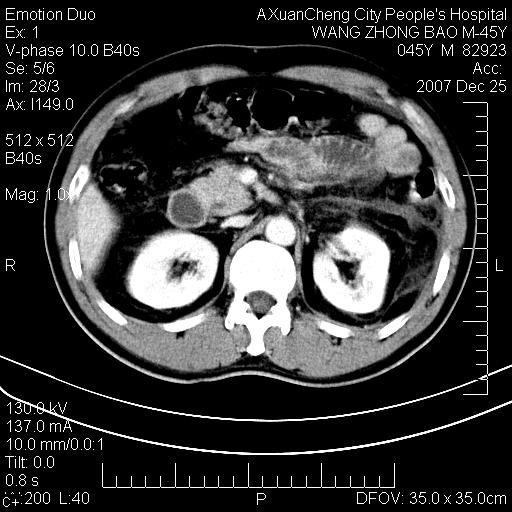

以下是引用卜一在2007-12-25 14:07:00的发言:[br]胰头钩部略增大,与十二指肠壶腹部关系密切,其内明显见软组织密度肿块,明显强化,但肠壁较光滑 柔软。考虑:炎性增生!建议消炎后复查!待除外壶腹部腺癌!

以下是引用zjzjr在2007-12-25 13:35:00的发言:[br]考虑正常的十二指肠乳头部,建议胃镜检查.

以下是引用qiuleiyu在2007-12-25 18:14:00的发言:[br]胰腺增大,周边渗出改变,肾前筋膜明显增厚,示少量积液.胆囊壁毛糙,周边少许渗出,胆总管壁厚,异常强化,然扩张不明显.结合病程急短;考虑;胆管炎,胆囊炎,胆源性胰腺炎可能大,请结合实验室检查及随访.

以下是引用lisihao在2007-12-25 14:23:00的发言:[br]急性水肿型胰腺炎[br]依据:1、胰腺弥漫性肿大,边缘稍毛糙;[br] 2、双侧肾周筋膜增厚,尤以左侧为甚(重要征象)[br] 3、双侧后胸膜增厚(刺激性炎症);[br] 4、结合病史,查血尿淀粉酶应该可以确诊。